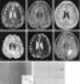

Gyriform cortical/subcortical T2 hypointensity

Acute cortical infarction

Acute subarachnoid hemorrhage

Meningitis

Subacute cortical infarction

Superficial siderosis